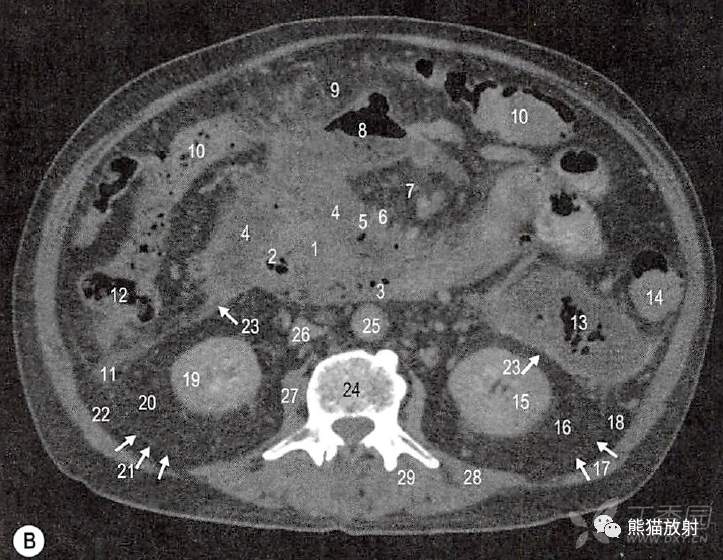

一例58岁慢性胰腺炎和胰周假性囊肿男性患者。

口服和静脉注射增强对比剂计算机扫描(CT轴位和矢状位)。

假性囊肿,包含气体和液体,胰周间隙扩大。融合筋膜的边界因为慢性炎症增厚,容易可见。

B.第4腰椎水平横断面;1.胰体的下部和胰钩突;2.十二指肠降部远端;3.十二指肠水平部;4.胰周积液(胰腺和十二指肠周围和前面);5.肠系膜上静脉;6.肠系膜上动脉;7.肠系膜;8.横结肠系膜的部分积气;9.横结肠系膜(与大网膜融合);10.横结肠;11.升结肠后面积液;12.升结肠;13.降结肠后积液(带气体);14.降结肠;15.左肾实质;16.左肾周间隙;17.左肾后筋膜(正常厚度,故较小);18.左肾旁后间隙;19.右肾实质;20.右肾周间隙;21.右肾后筋膜;22.右肾旁后间隙;23.肾前筋膜(因慢性炎症而增厚);24.第4腰椎体上部;25.腹主动脉;26.下腔静脉;27.右腰大肌;28.左侧腰方肌;29.左侧竖脊肌群。

C.矢状切面;1.胰颈;2.前部积气;3.后部积液;4.腹腔干;5.肠系膜上动脉;6.左肾静脉;7.腹主动脉;8.膈脚;9.肝左叶;10.胃窦;11.横结肠系膜的部分积气;12.横结肠;13.渗入肠系膜的部分积液;14.十二指肠水平部。